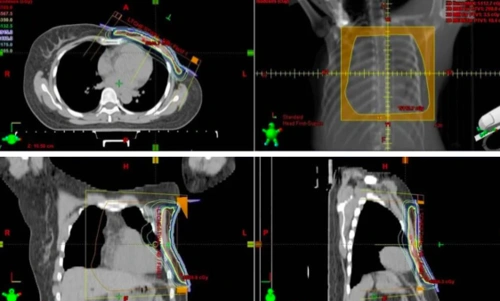

左乳癌保乳术后混合调强放疗中利用多叶准直器遮挡技术减少心脏受照